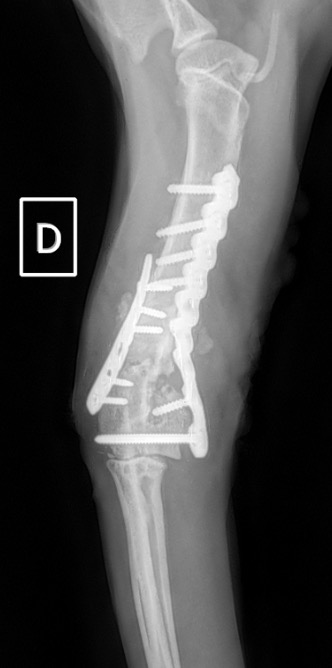

Notre préférence va vers le placement de deux plaques humérales : une médiale de la plus grande taille possible et l’autre latérale, généralement d’une taille inférieure à la première. Dans l’exemple 1 (chat européen), une plaque de 2 mm est utilisée médialement et une plaque de 1,5 mm latéralement. Dans l’exemple 2 (chien Malinois), une plaque de 3,5 mm est utilisée médialement et une plaque de 2,7 mm latéralement.

Exemple 1 :

Figure 2 : Post-Op Immédiat